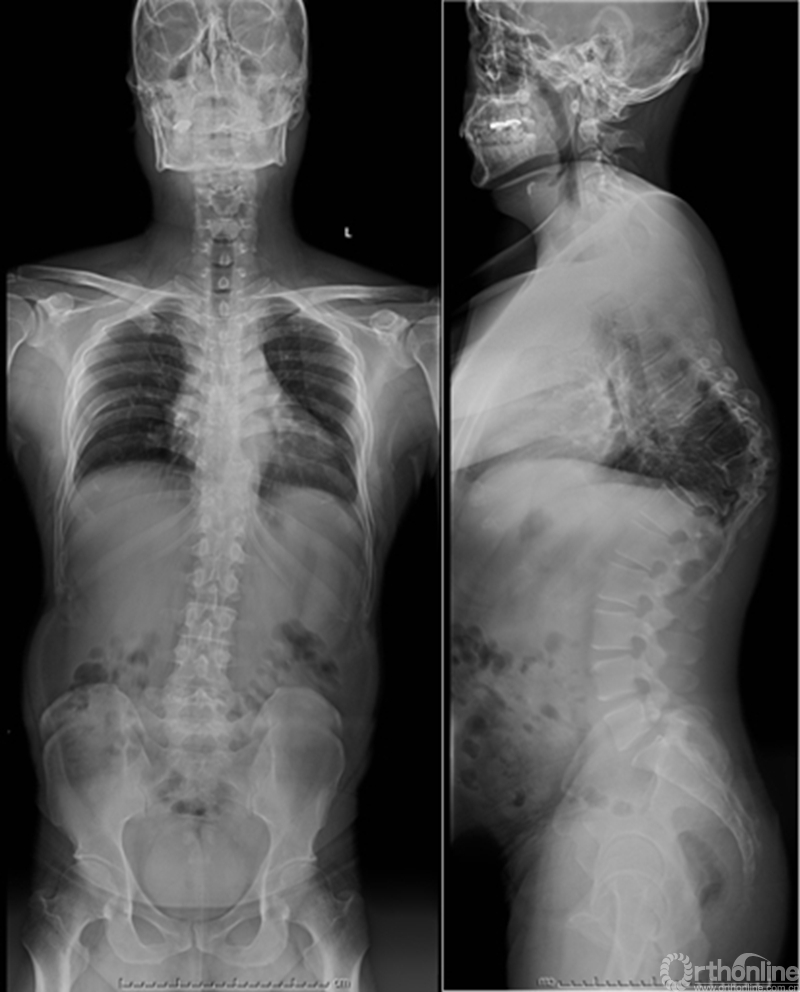

众所周知,脊椎结核后突畸形是结核病严重的后遗症之一。不仅影响患者外表仪容和心理,还可能出现晚发病灶造成截瘫。30多岁的小李就是一位脊柱结核后造成后凸畸形伴截瘫的患者,其畸形角度高达90度。针对此类患者的治疗大多就是截骨矫形,手术创伤大不说,椎体切除后造成的脊柱失稳等一系列后遗症也是令医生和患者担忧的。为解决临床上的这类问题,丁文元教授对传统的PVCR截骨技术进行了简化和改良,即后路单侧截骨部分椎体切除固定矫形术(UPVCR)入路,该技术采用后方单侧截骨,切除部分椎体、相邻椎间盘大部,保留对侧椎弓根及部分椎体,重建置入钛网支撑。随后,丁文元教授通过UPVCR技术对小李实施了手术,经过家人悉心地照顾,小李术后肌力恢复的良好,很快就出院了。三个月复查时竟是自己走路来的,临床疗效让患者及家人很是满意。

患者术前资料

患者术后资料